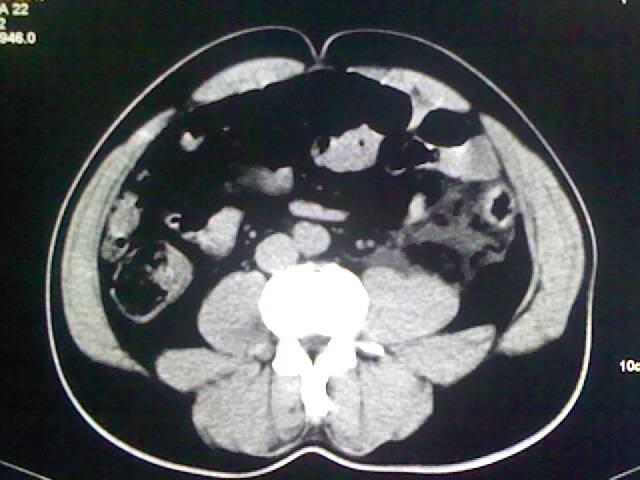

以下是引用zsl6918在2009-2-7 7:29:00的发言:[br]请提供介入的方式方法,肾及输尿管改变考虑与介入损伤有关,漏了,尿液外渗。

以下是引用余辉在2009-2-7 8:27:00的发言:[br]可能是硬化剂烧穿囊壁进入肾盂输尿管了,尿漏。不除外介入或碎石术后合并感染[br]患者术后怀疑结石,接着就碎石了?就怀疑没有确诊吗?碎石用的什么方法?气压弹道还是体外超声?如果这样的话责任人都难找

以下是引用随光逐影在2009-2-7 8:46:00的发言:[br]支持3楼意见。[br]另:不排除左肾及肾周感染可能。